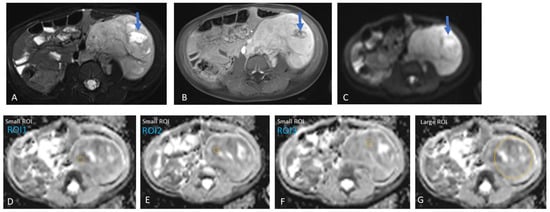

2.3.2. MRI Interpretation